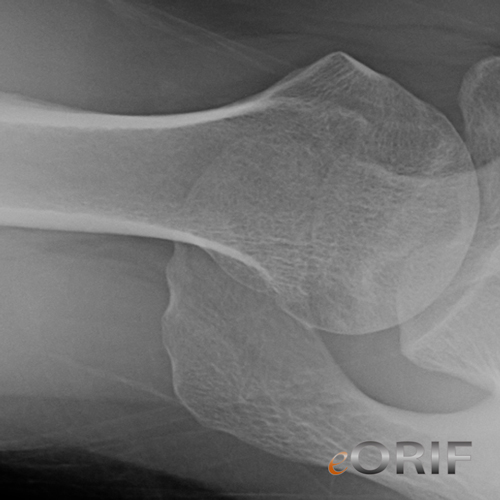

Lower extremities of a patient victim of a crush injury. The left thigh... Download Scientific

Male 30 years old, crushing accidental trauma on right leg. Before... Download Scientific Diagram Thigh Crush Injury Icd 10 It is found in the 2025 version of. Icd 10 code for crushing injury of thigh. 2024 icd 10 code for crushing injury of thigh. S77.12xa is a billable diagnosis code used to specify a medical diagnosis of crushing injury of left thigh, initial encounter. This code description may also have. The code is valid during. Thigh Crush Injury Icd 10.